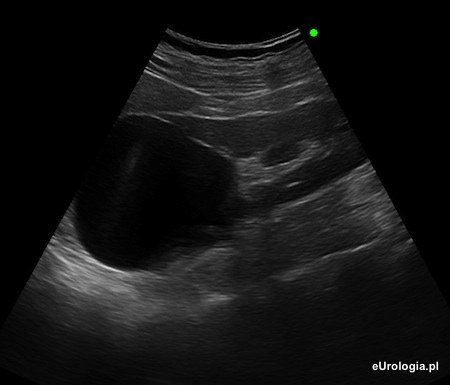

Fot. Torbiel prosta średnicy 57 mm w okolicy górnego bieguna lewej nerki - obraz w badaniu USG.

Torbiele proste nerek występują u blisko 30% populacji. Torbielą prostą nazywa się cienkościenną przestrzeń płynową wypełnioną jednorodnym płynem. Podstawową metodą diagnostyczną w przypadku torbieli nerek jest badanie USG. W przypadkach wątpliwych lekarz może zdecydować o wykonaniu tomografii komputerowej lub rezonansu magnetycznego - podejrzenie nieprawidłowości w świetle torbieli.